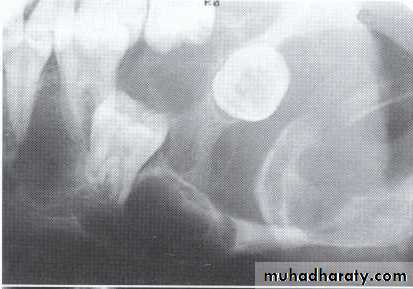

*A 55 year old man with an expansile multilocular radiolucency of the left mandible. The swelling had been noticed by the patient for approximately one year.

A: Odontogenic fibroma

B,C,D:Odontogenic myxoma.Odontogenic Adenomatoid Tumor (OAT)